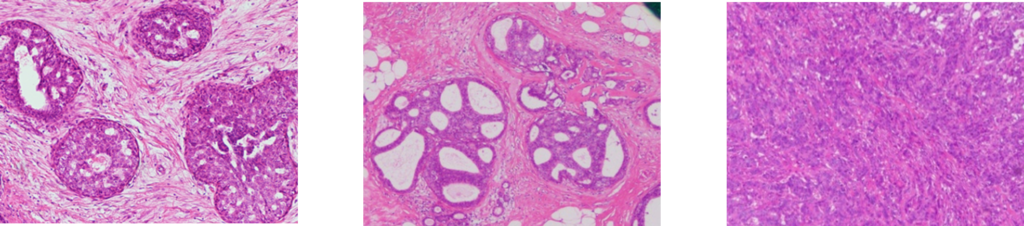

In collaboration with Tohoku University and others, we are developing AI to detect breast cancer lesions from pathology images. On October 7, 2022, we announced that the results of our joint research on a breast cancer detection model in histopathological micrographs4) using a single-shot multibox detector (SSD), an AI-based object detection method, were published in the the Journal of Pathology Informatics. When the detection model classified cancers into three classes (benign, non-invasive cancer, invasive cancer) or two classes (benign, malignant), the accuracy was 88.3 % and 90.5 %, respectively.

After learning data consisting of 943 microscopic images of intraoperative frozen sections of breast cancer3), an SSD model was developed. The diagnostic accuracy of breast cancer was evaluated using 65 intraoperative frozen section images.

benign non-invasive cancer invasive cancer